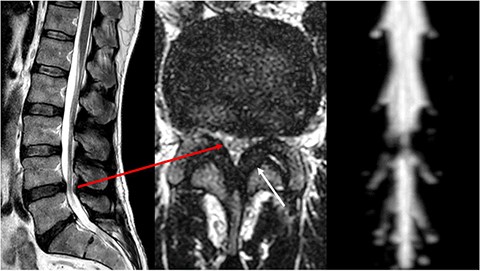

A subsequent operation with decompression via interlaminar fenestration led to clinical improvement without complete resolution of the symptoms. The histology obtained showed increased amyloid deposition in the ligamenta flava. In parallel, an increasing cardiomyopathy developed, with left ventricular hypertrophy and reduced contractility confirmed by ultrasound and cardiac MRI (Fig. 3). Additional 2,3-dicarboxypropane-1, 1-diphosphonate (DPD) scintigraphy led to a pathognomonic storage in the area of the heart muscle (Fig. 4) and the thigh muscles. Over the course of the disease, the patient experienced significant weight loss and recurrent, sometimes bloody diarrhoea. Colonoscopy with sampling of the rectum confirmed the presence of an amyloid-associated enteropathy. The patient also developed stage 2 renal insufficiency.

Scintigraphy with single photon emission computed tomography (SPECT) shows markedly increased tracer uptake in the area of both atria and ventricles with septal emphasis.